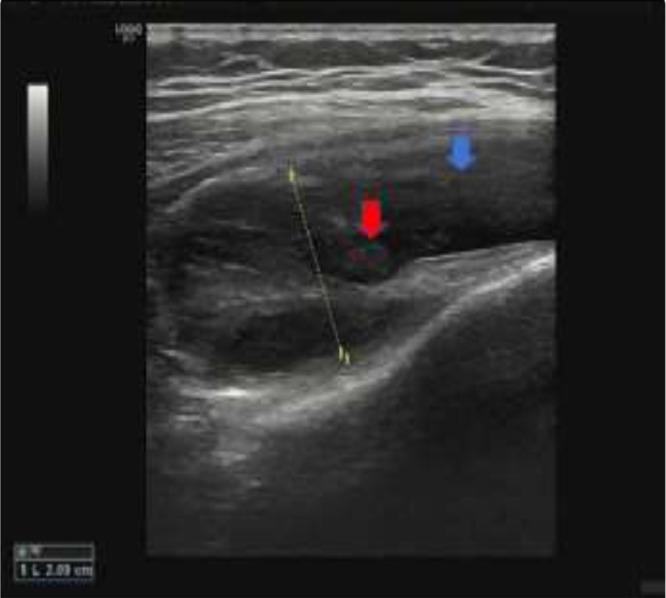

Pigmented villonodular synovitis is a rare proliferative process, especially in children. Pigmented villonodular synovitis can affect the synovial joint, tendon sheaths, and bursa membranes. Within synovial joint involvement, it is commonly seen in the knee joint but hip, ankle, shoulder, wrist, and other joints can be involved. The appearance characteristic is found on a magnetic resonance imaging scan. Complete excision and synovectomy are the usual treatment. In this article, we report a case of pigmented villonodular synovitis of the knee in a 12- year-old girl who underwent total synovectomy after the diagnosis was confirmed by biopsy. Three years after surgery, neither recurrence nor joint degeneration was found. The osteochondral defect at the tibial plateau was filled with calcium phosphate bone paste.

色素沉着绒毛结节性滑膜炎是一种罕见的增殖性病变,在儿童中尤为少见。色素沉着绒毛结节性滑膜炎可累及滑膜关节、腱鞘和滑囊。在滑膜关节受累的情况下,常见于膝关节,但髋关节、踝关节、肩关节、腕关节和其他关节也可受累。其外观特征可通过磁共振成像扫描发现。完整切除和滑膜切除术是常用的治疗方法。在本文中,我们报告了一例12岁女孩膝关节色素沉着绒毛结节性滑膜炎的病例,该女孩在活检确诊后接受了全滑膜切除术。术后三年,未发现复发及关节退变。胫骨平台的骨软骨缺损用磷酸钙骨糊填充。